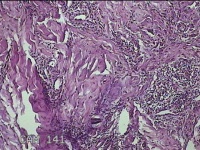

左侧腰部皮肤息肉组织

性别

男

年龄

40岁

临床诊断

皮肤和皮下组织良性脂肪瘤样肿瘤,其他部位的

一般病史

发现左侧腰部皮肤息肉组织5年余。

标本名称

大体所见

灰白暗红色息肉样组织1.7x1.3x0.3cm一块,表面糜烂,切面灰白暗红色,质软。